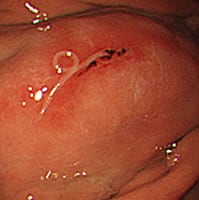

胃アニサキス症

前日から胃痛と嘔気があり、胃カメラをやったところアニサキス虫体がいました。その場ですぐに虫体を摘出し症状改善しました。

さばやイカなどを食べた後に胃が痛くなったら、アニサキスの可能性ありますのでご相談ください。